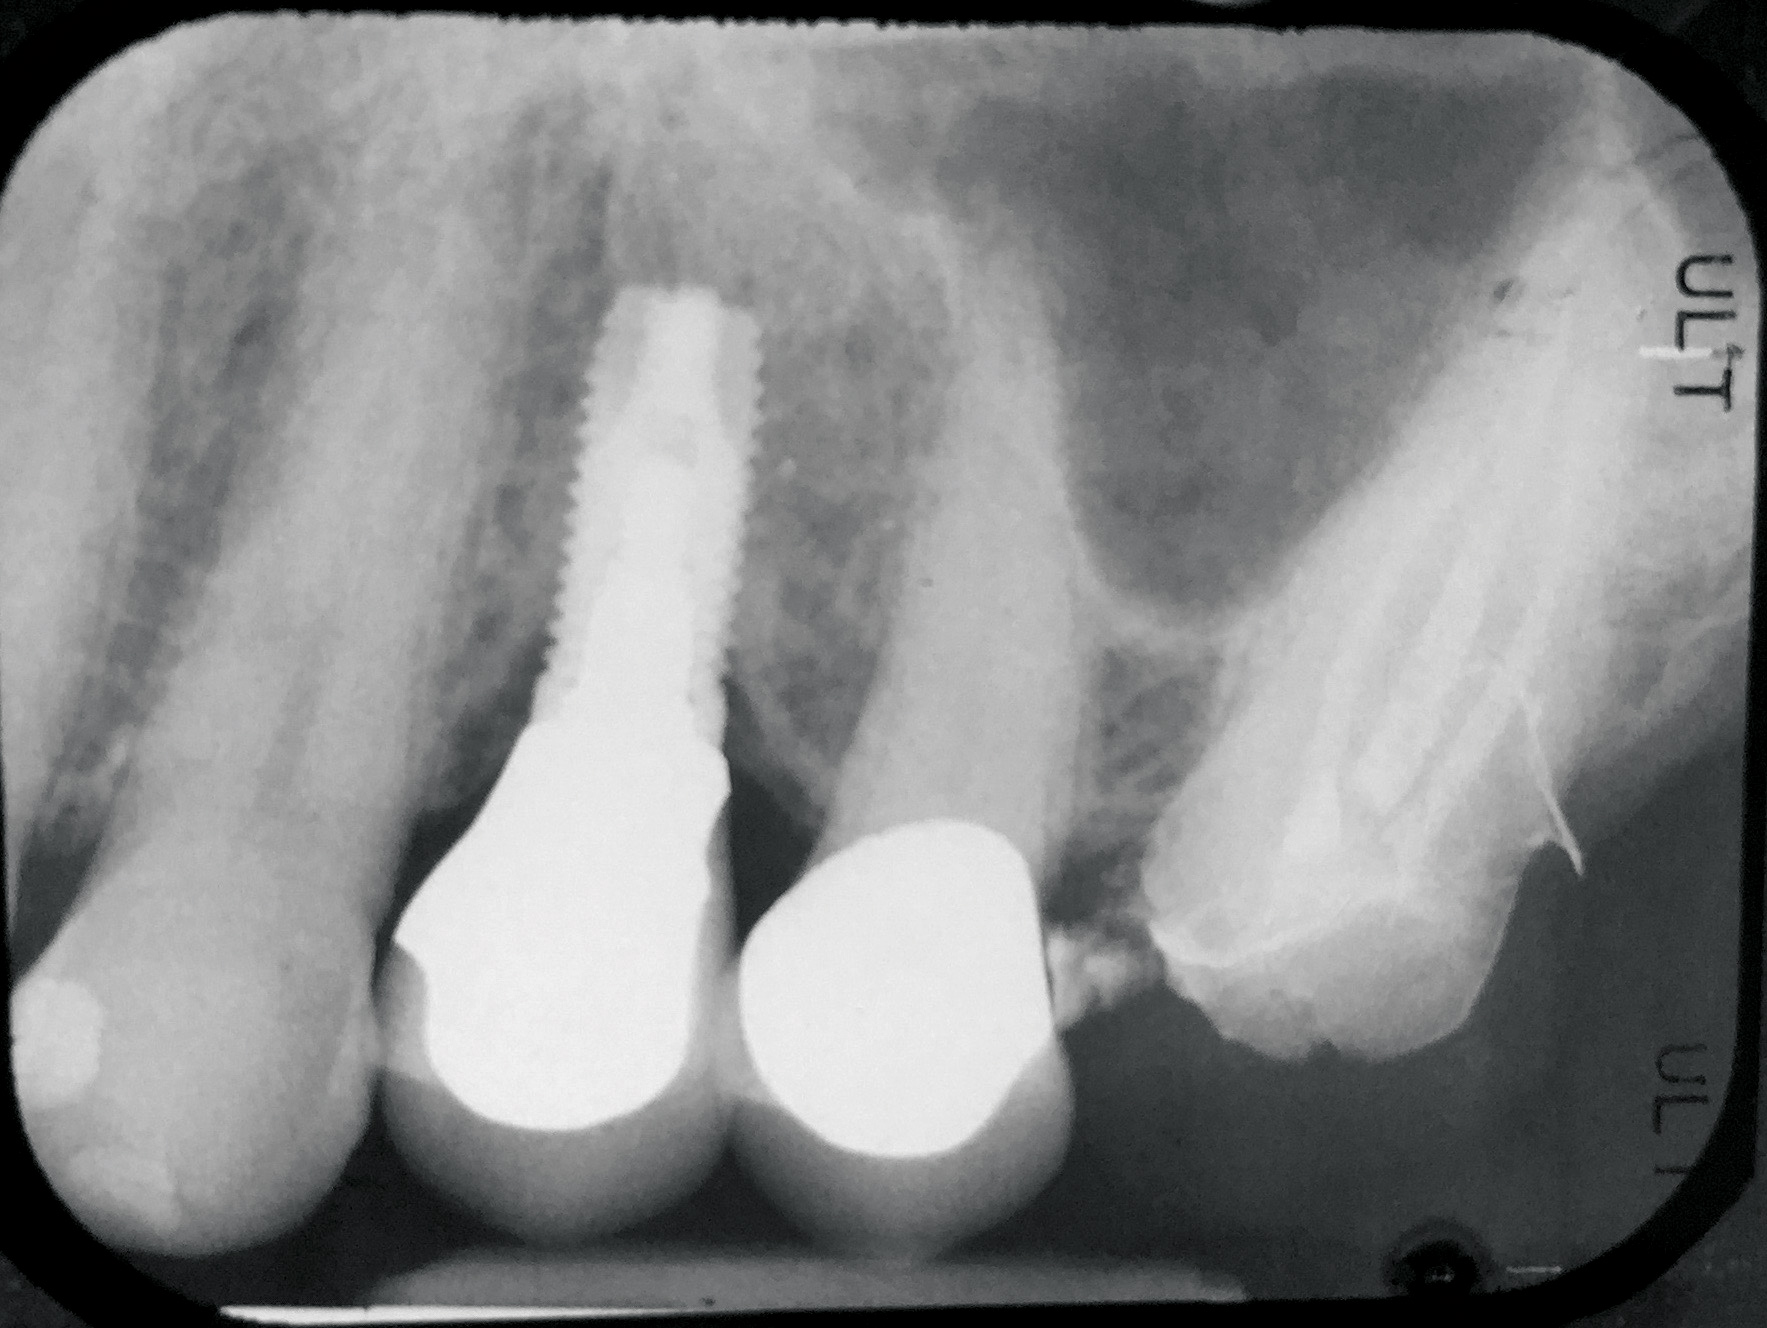

Fig 16. Radiograph depicting closed contact at time of implant insertion.

Figure 16

Fig 17. Open proximal contact between implant and adjacent tooth 3 years post insertion.

Figure 17

During the initial planning phase for implant therapy, the dental practitioner should not assume that the existing position of the teeth within the dental alveolus will remain stationary throughout the patient’s lifetime. Long-term follow-up of implant restorations has proven that often it does not remain stationary, regardless of the age of the patient. Open contacts have frequently been reported between implants and adjacent teeth.30

Open proximal contacts between implants and adjacent teeth have been attributed to ongoing craniofacial growth31 and vector forces mesializing tooth position (Figure 16 and Figure 17).32 These changes, particularly in the esthetic zone, can contribute to differences in incisal edge position, gingival margin height, and the facial contour and alignment of the dental arch (Figure 18 and Figure 19).31 Jemt et al30 studied a population of 28 consecutive anterior implant crowns followed for 15 years. During this time, only 8 patients demonstrated no movement of the adjacent teeth; 55% of adjacent teeth displayed palatal tooth movement, predominately in the female population.30 Shifting of teeth can contribute to occlusal changes leading to uneven occlusal load and distribution among the arch.31 Similar to adjacent open contacts between teeth, any open contact can lead to food impaction/accumulation, pocketing, and inflammation of the interdental tissue.

Greenstein et al32 made several suggestions for the treatment of open interproximal contacts, including discussing with the patient prior to treatment the possibility that therapy may be needed for the implant crown. Also, the need for retrievability of the crown should be considered so that porcelain may be added to the crown, and adjacent teeth should be modified to include broad, flat contacts. In addition, in circumstances when the crown cannot be removed, the contacts may be added to the adjacent teeth.